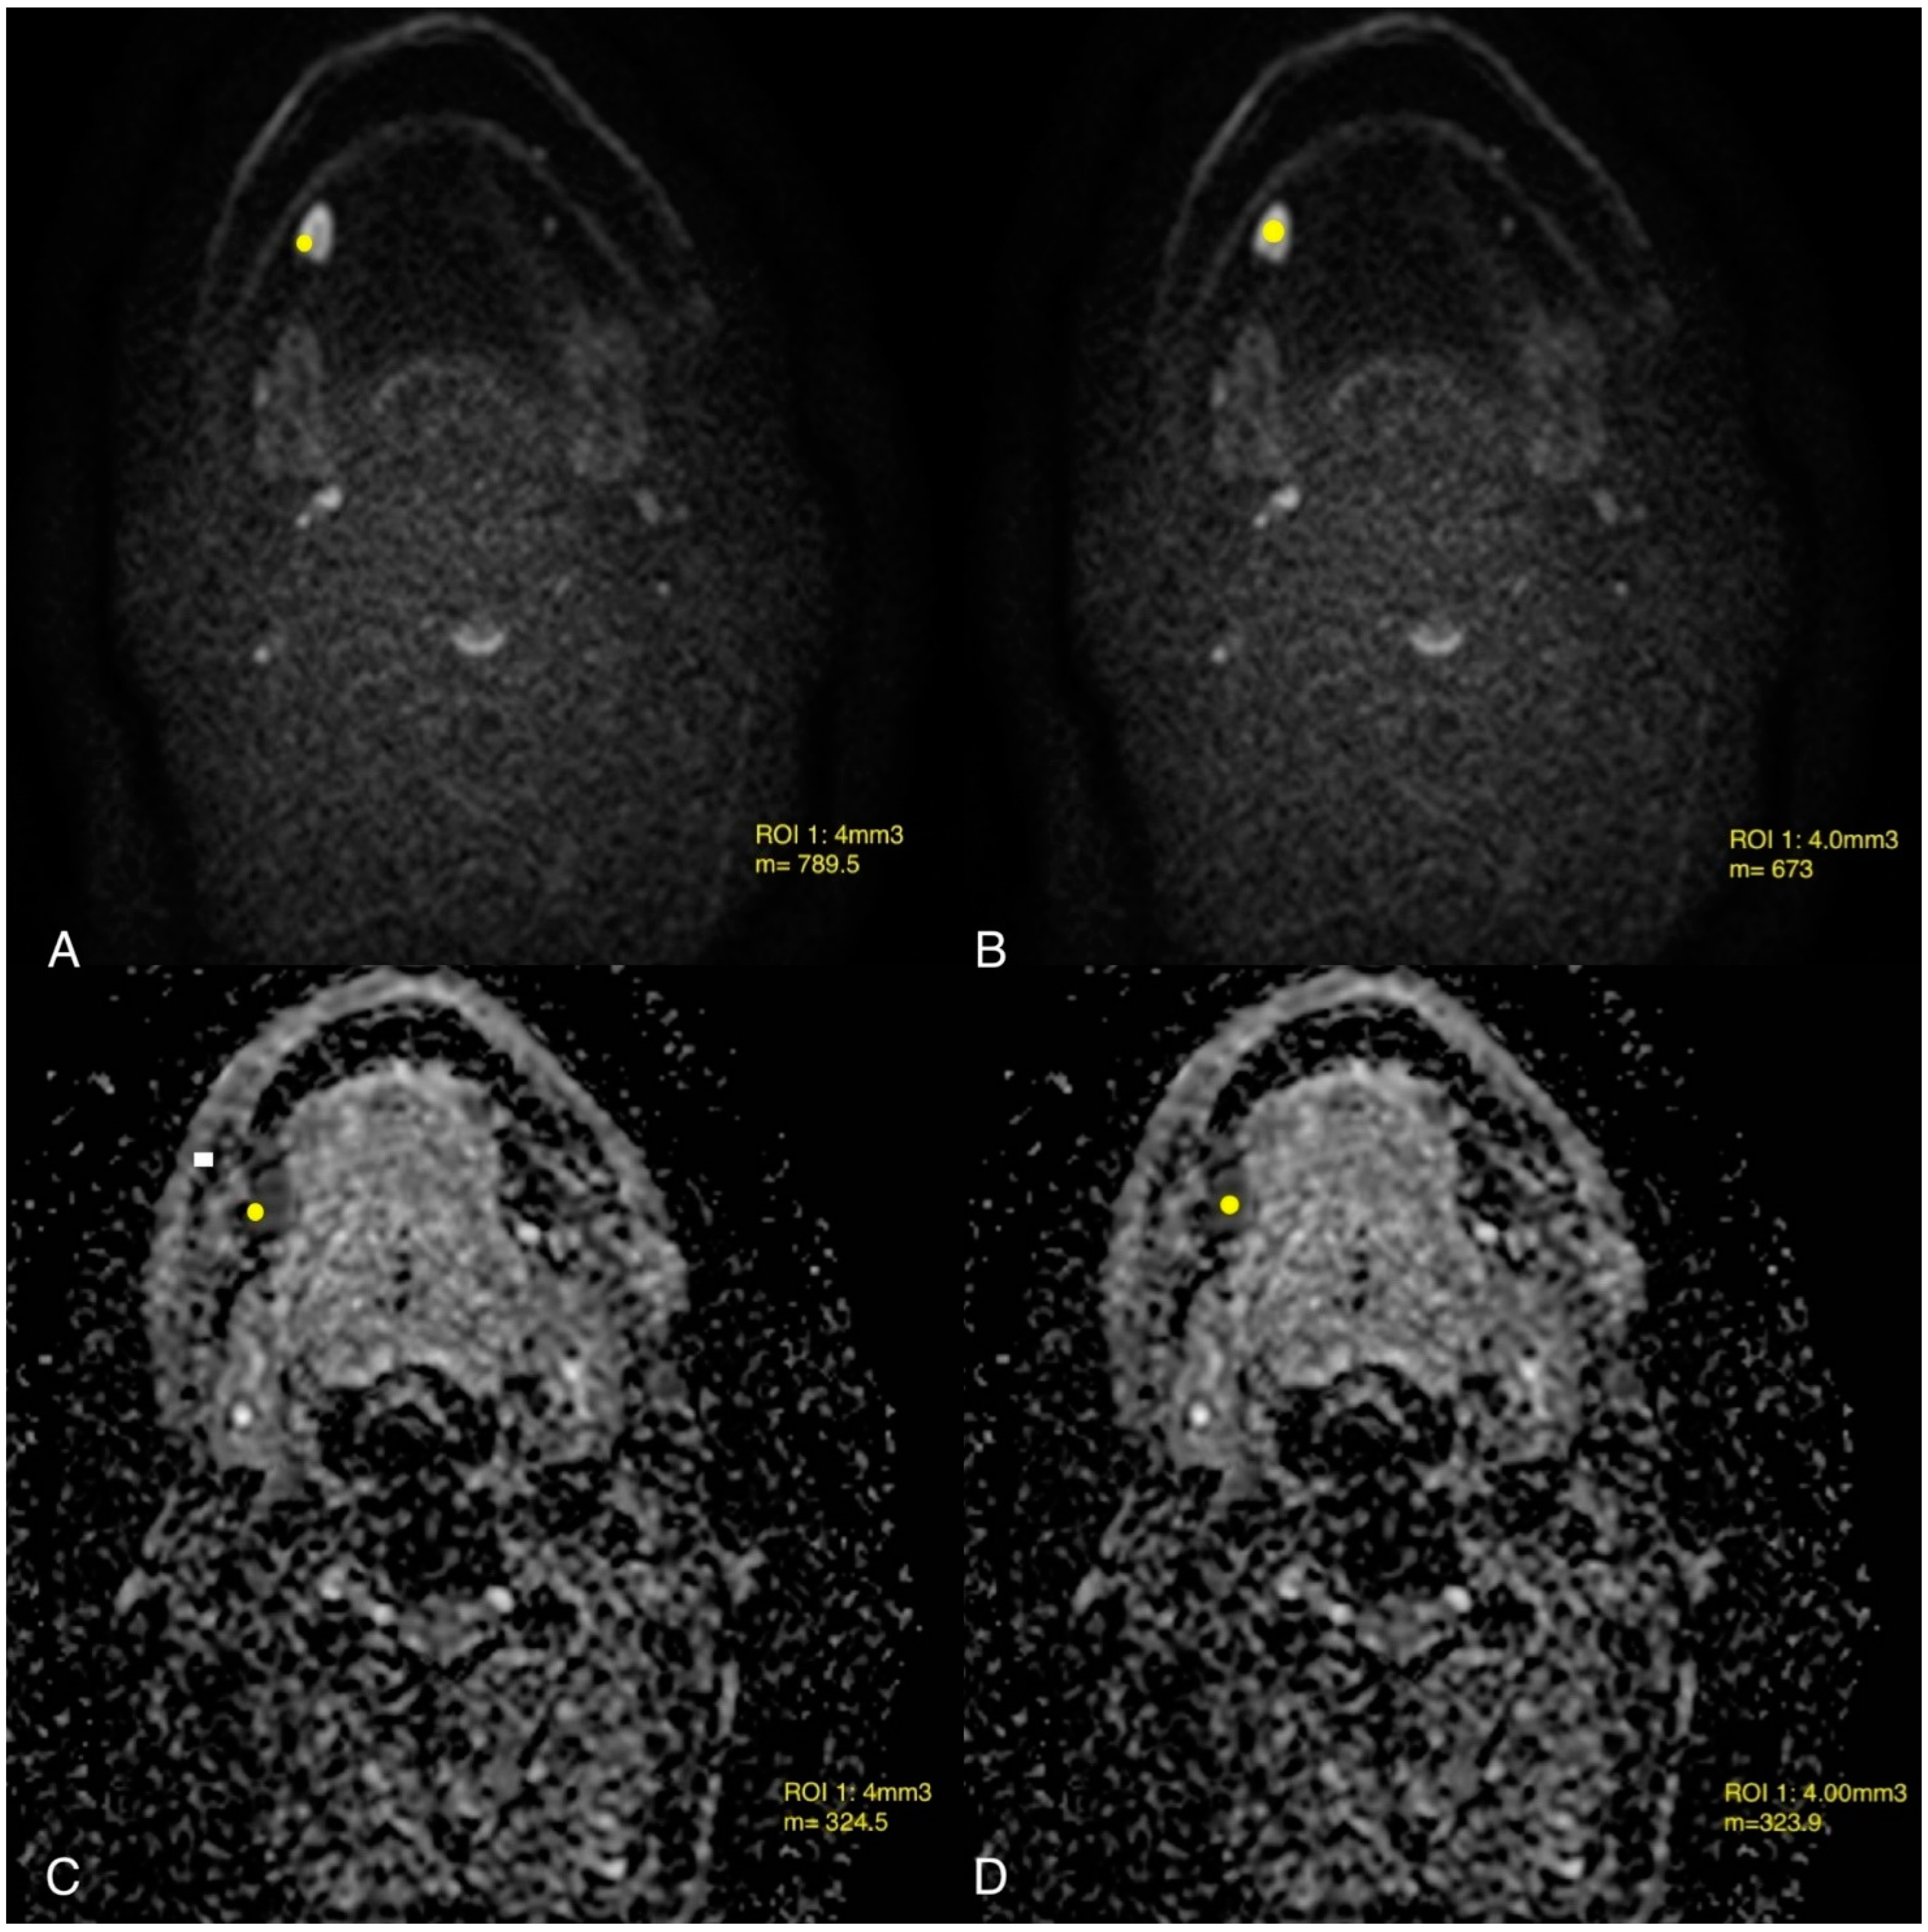

- Jović, A.; Fila, J.; Gršić, K.; Ivkić, M.; Ozretić, D. Diffusion-weighted MRI: Impact of the size of the ROI in detecting metastases in subcentimeter lymph nodes in head and neck squamous cell carcinoma. Neuroradiology 2020, 62, 987–994. [Google Scholar] [CrossRef] [PubMed]